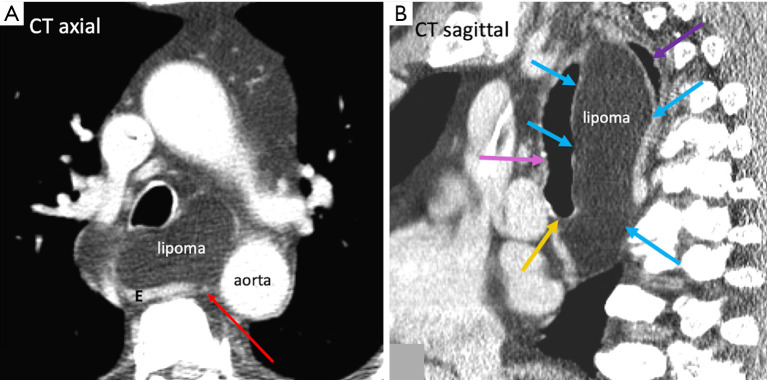

While it is not uncommon to see central mediastinal diseases on cross-sectional imaging, it is important to understand the pathway influencing the spread of disease at a radiological point of view. The advent of minimally invasive thoracic surgeries has led to the discovery of unknown tissue planes in the mediastinum such as the aorto-esophageal (AE) and aorto-pleural (AP) ligaments. In particular, the AE ligament is a portion of the mediastinal visceral fascia, which courses from the anterior aspect of the aorta to the left lateral aspect of the esophagus. It can be visualized on computed tomography (CT) and magnetic resonance imaging (MRI); it courses longitudinally from the level of the aortic arch to the level of the diaphragm. This recently discovered unknown anatomy aids us in understanding the possible pathway of spread of disease processes such as air, fluid, and soft tissue in the mediastinum. In addition, it acts as an important anatomical landmark in determining the location of lymph node metastases from esophageal cancer, which will further influence the possibility of thoracic duct resection/sparing. Finally, the AE ligament can be utilized in the preoperative planning of minimally invasive thoracic surgeries and can potentially be used as a dissection plane during esophagectomies.